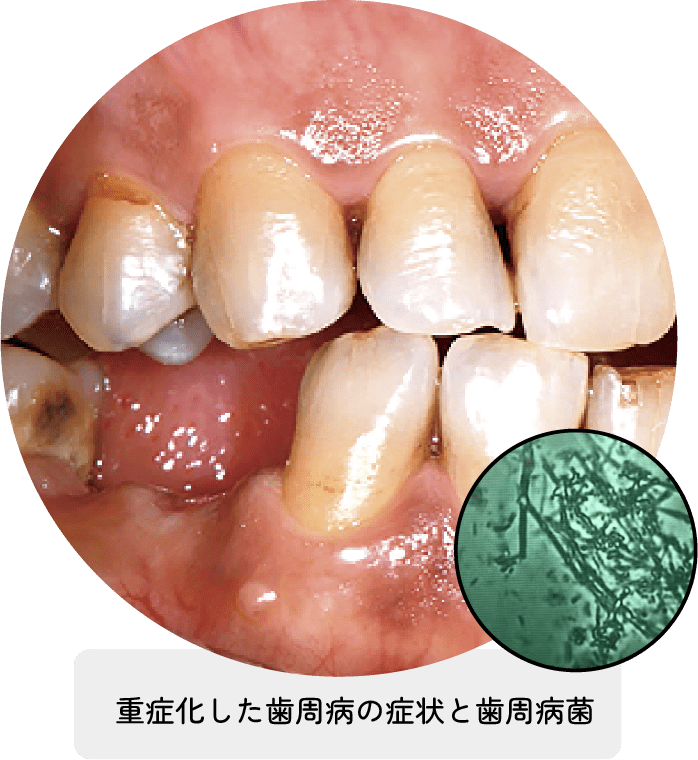

歯を失う原因の第1位といわれる歯周病。歯ぐきの腫れや出血から始まり、徐々に口臭が強くなり、歯を支える骨が溶け始めます。重症化すると歯がグラつき、最終的には抜け落ちてしまう怖い病気です。重症化する前にキチンと治療を受けることが大切です。

歯周病は歯の周りの歯ぐきや歯を支える顎の骨が失われていく病気です。歯ぐきの隙間から身体の中に入り込もうとする細菌による感染症です。初期段階では、痛みなどの症状がないサイレント・ディジーズと呼ばれ静かに進行していきます。

歯が抜けてしまう怖い病気